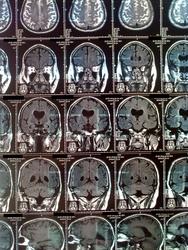

Уважаемый коллега!Большая просьба-в кадр помещать по 4 снимка максимум.

Очень мало нормальных сагиттальным снимков, хотя по СКТ видно, что ретроцеребеллярные и основная цистерны расширены-трудно оценить мозжечок.

Полость прозрачной перегородки также имеется.Гидроцефалия смешанная, преимущественно за счет внутренней.Не исключено наличие очагов глиоза субкортикально, но ( повторюсь)-по таким снимкам трудно оценить структурные изменения.

отсутствие прозрачной перегородки- гипо или агенезия, диспластические изменения каудальных отделов червя мозжечка с компенсаторным цистернальным расшиернием в ЗЧЯ. Расшиерны толко боковые желудочки, III-ий не изменен. Обезыствлены хориоидальные сплетения. Уменьшен объем мозжечка. Перивентрикулярно определяются горизонтальные и вертикальные поввышенные по Т2 ВИ -похоже на артефакты. Это все, что удалось разглядеть. Можно предположить развите спино-церебеллярной дегенерации.